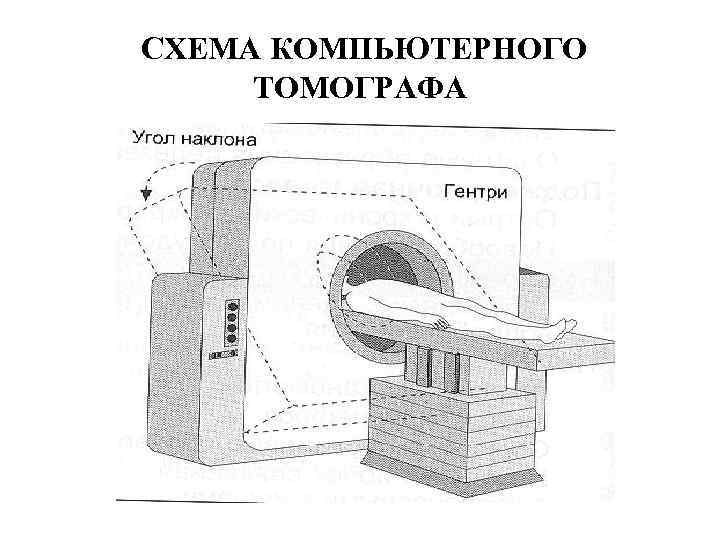

СХЕМА КОМПЬЮТЕРНОГО ТОМОГРАФА

СХЕМА КОМПЬЮТЕРНОГО ТОМОГРАФА